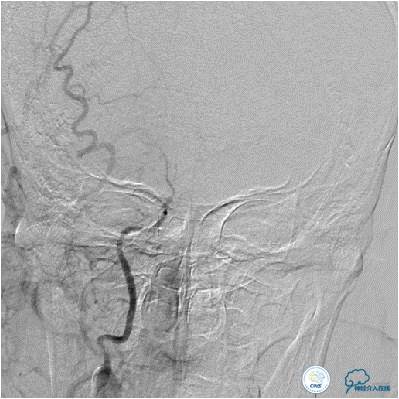

患者入院后,完善颅内CTA(图1)及血管造影(图2~3)检查,发现右侧颈内动脉颅内段闭塞,右侧大脑前动脉依靠左侧颈内动脉系统通过前交通动脉供血,右侧大脑中动脉供血区则依赖于右侧大脑前动脉(ACA)软脑膜代偿供血,左侧大脑中动脉闭塞,依靠一少见血管代偿供血,该血管起自左侧大脑前动脉A2段起始部,代偿供应左侧大脑中动脉供血区。由于该患者灌注CT(图4)未见明显低灌注区,遂给予患者抗血小板、降脂及控制危险因素治疗出院。出院后电话随访未再出现过上述症状。

图1:三维造影提示左侧大脑中动脉闭塞,左侧大脑中动脉由一异常血管供血,考虑为Heubner返动脉。

图2:患者右侧颈内动脉造影提示右侧大脑中动脉次全闭塞,血流缓慢。大脑前动脉未见显影。